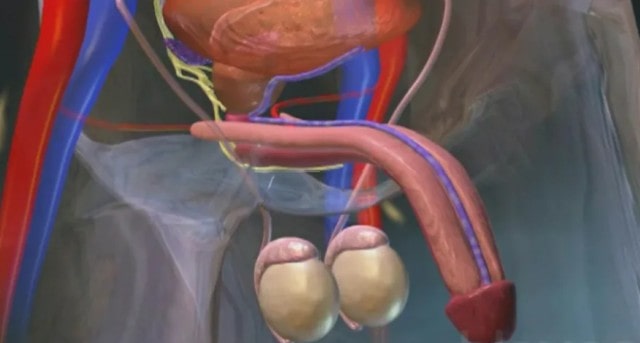

Męski organ płciowy ma dwie główne tętnice grzbietowe: jedną, przez którą przepływa krew, i żyłę, przez którą odpływa. Erekcja jest możliwa dzięki zastawkom w żyle grzbietowej, które zatrzymują przepływ krwi i utrzymują ją w ciałach jamistych.

Męski organ płciowy ma dwie główne tętnice grzbietowe: jedną, przez którą przepływa krew, i żyłę, przez którą odpływa. Erekcja jest możliwa dzięki zastawkom w żyle grzbietowej, które zatrzymują przepływ krwi i utrzymują ją w ciałach jamistych. - Czy podobne rozwiązania są dostępne w Polsce?